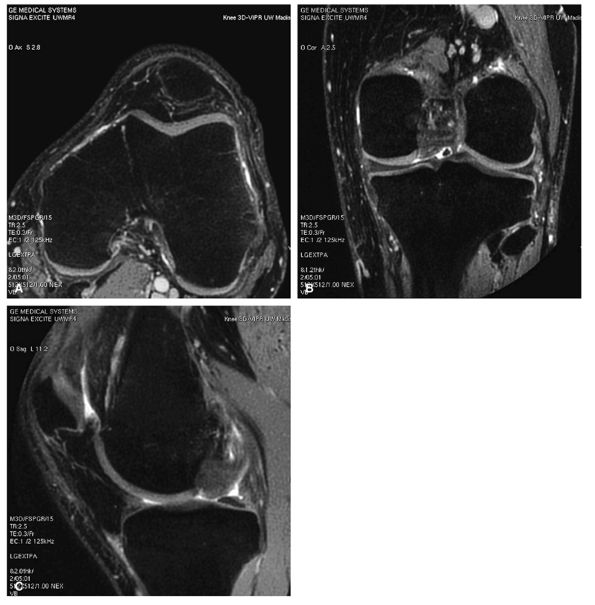

![]() |

|

FIGURE 1.22 ● Example of a totally isotropic 3D sequence, 3D-VIPR. Raw data are acquired in a projection-reconstruction mode (not like 2D and 3D Fourier). Reformations (A –C) from a unique 3D data set of 0.4 × 0.4 × 0.4 reconstructed voxels, acquired in 5 minutes 1 second. The sequence also provides an intrinsic fat suppression and a T1/T1 image contrast (steady-state free precession). (Work in progress, developed by University of Wisconsin, Madison)

FIGURE 1.25 ● Examples of diffusion tensor MRI in calf muscle. (A) Blue indicates diffusion along the S-I axis. (B) Fractional anisotropy shows the degree of anisotropy regardless of direction. Control image (C) and fiber-tracking display using two different rendering techniques (D, E).